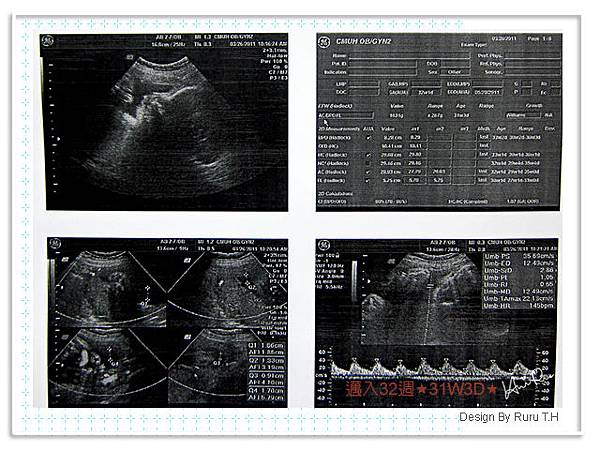

接近8個月了,整個孕期目前體重約增加了6公斤,跟一個月前沒甚麼差別,不過BB大了一周,肚圍也大約到了102cm,也不知他是怎麼辦到的,很多人說我的肚子沒有很大,大多猜測我約6個多月,我想可能是往前長的緣故,醫師替我證明了,不只大,還超過快一周了><

這傢伙的頭圍好像粉大有35W,以後可以對他唱大頭大頭下雨不愁~

這次檢查報告好正弟弟咧~頭趴著,四肢藏在身體下面,所以超音波師阿姨沒辦法判讀,但是醫生阿北說上次檢查沒異常大致上是沒有問題了。

超音波師說,BB這個時期已經很大了拍不到全身,會超過鏡頭,這也難怪到後期的超音波醫師都很快速的檢查掃過,原來是這麼一回事啊!

31W3D第八次產檢◎大一周◎